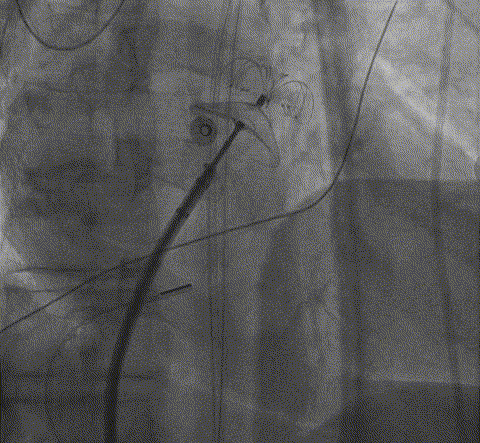

ICE扫描心耳评估血栓位置

渐进式将血栓推行远端

面对左心耳口部存在不稳定血栓这一核心难点,心血管内二科迅速联合神经内科、介入医学科等多学科专家进行深入评估。为最大程度确保治疗安全,团队最终确定了结合心腔内超声引导与“脑保护装置下带栓封堵”的个体化手术方案,为手术提供了至关重要的“双重保险”。

术中,治疗团队在心腔内超声和脑保护装置的全程守护下,精准处理了血栓,并成功释放封堵器。术后即时评估显示,治疗达到了预期目标——将血栓完全封堵左心耳内,且术中未发生任何血栓脱落并发症。手术取得成功!